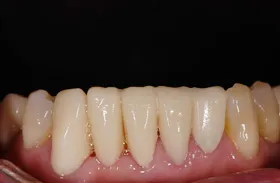

他院で「歯槽膿漏は治らない」と言われ、当院にご来院されました。歯が乱ぐいのため、歯並びもよくしたい、下は歯を既に失っているので噛めるようにもなりたい、またコーラスをされていて人前で口をあけることが多いので、できるだけ見た目を意識した治療をしてほしいとのご要望でした。

■治療(仮歯装着)後